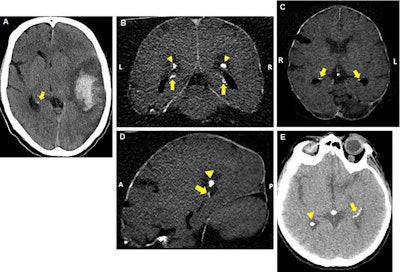

Axial reconstructed brain CT scans of patients with mild (A), moderate (B-D), or severe (E) hippocampal calcifications (indicated by arrows). Image courtesy of Dr. Pim de Jong, PhD.Hippocampal calcification

A total of 380 (19.1%) patients had hippocampal calcifications on their CT scans based on a reading by one of two trained physicians. The physicians rated each case based on the highest degree of calcification -- absent, mild, moderate, or severe -- with "good" interobserver agreement between the readers.